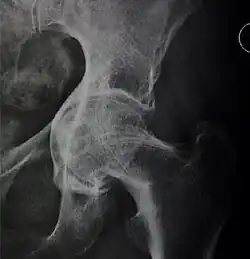

Measurements

- Fossa/ilioischial relationship: In normal conditions the floor of the acetabular fossa is lateral to the ilioischial line by 2 mm in men and 1 mm in women. When the acetabular floor overlaps or overpasses the ilioischial line, the diagnosis of coxa profunda can be made. Nevertheless, coxa profunda had been found in 76% of asymptomatic hips, mainly in women. Therefore, this as an isolate criterion is not enough to make the diagnosis of pincer-type impingement. A more severe condition is protrusio acetabuli, diagnosed when the femoral head overlaps or overpasses the ilioischial line.[3]

- Joint space: In the adult hip, normal joint space ranges from 3 to 5 mm and must be uniform. Values under 2 mm are consistent with joint space narrowing.[3]